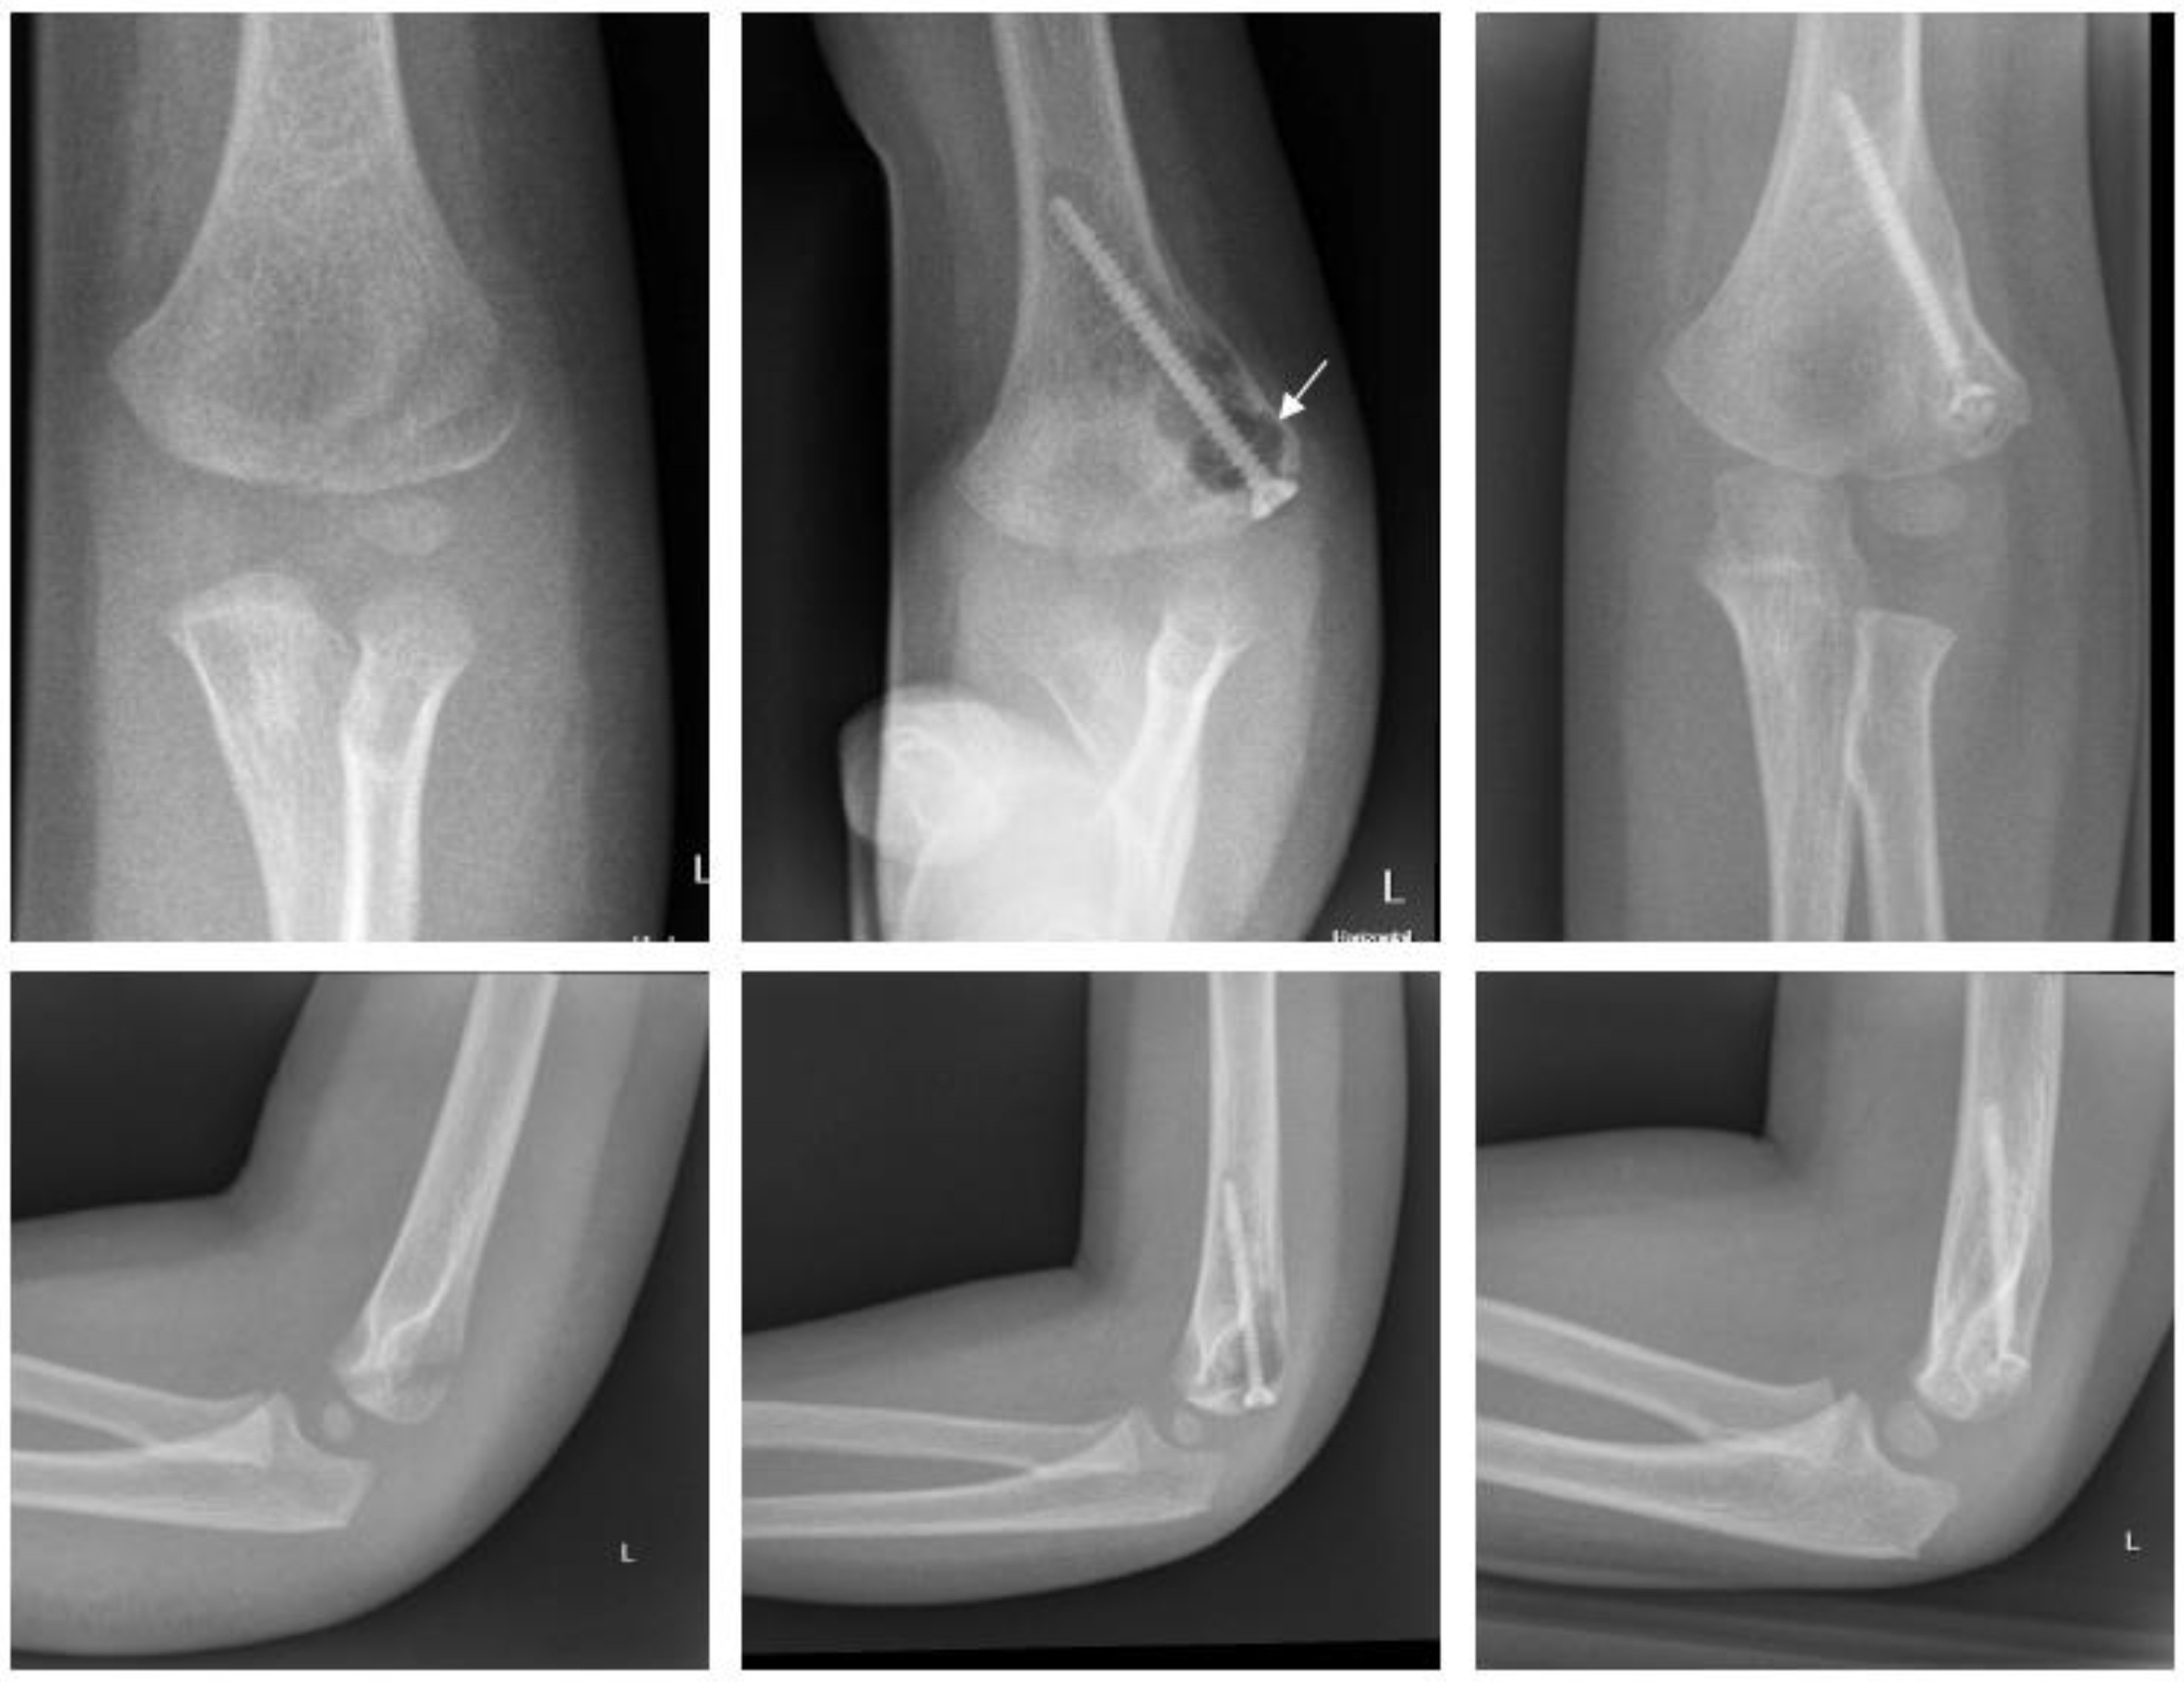

2.4.2. Fracture of the Medial Epicondyle

2.4.3. Fracture of the Lateral Condyle